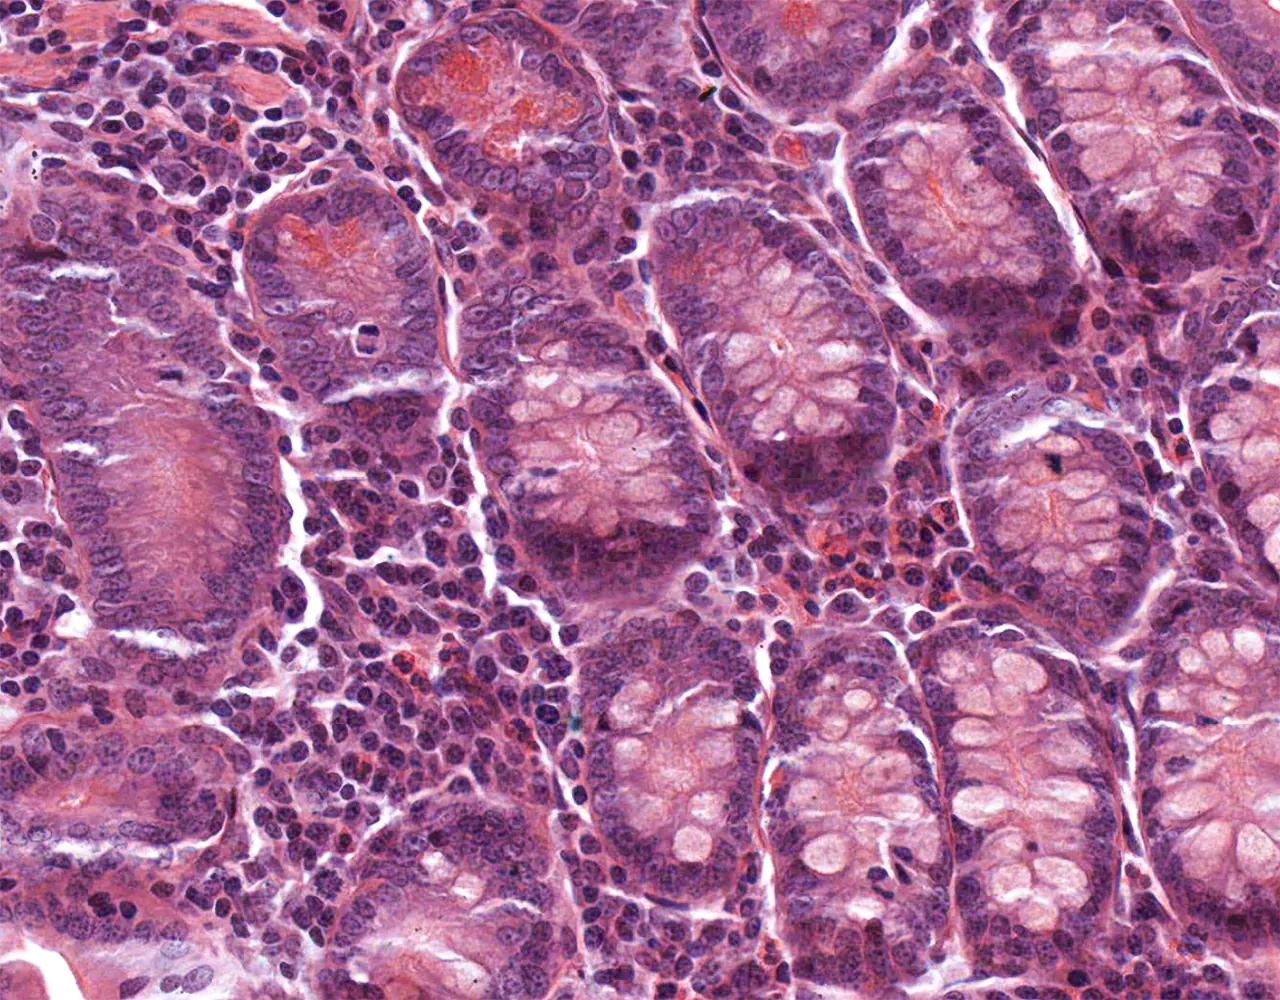

- The absorptive surface area of the small intestine is amplified by three structural levels: plicae circulares, villi, and apical microvilli forming the brush border.

- Microscopically, the wall is composed of 4 layers from the inside outward: mucosa, submucosa, muscularis propria, and serosa.